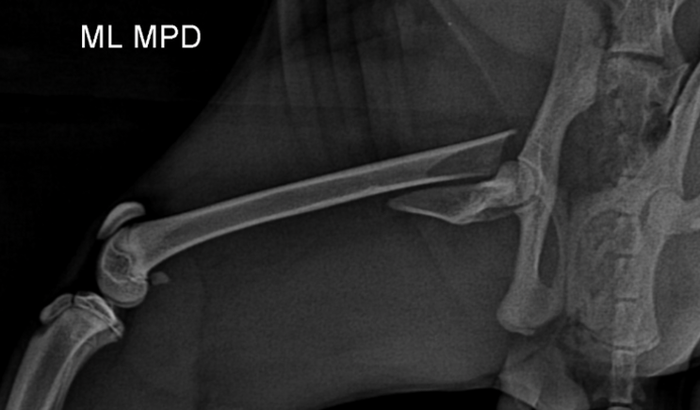

Mas recentemente eu fugi (minha humana diz que eu sou muito atrevido) e acabei fraturando meu fêmur, que é um osso tão importante quanto o de vocês, humanos. Estou sentindo muita dor e preciso de uma cirurgia para melhorar.